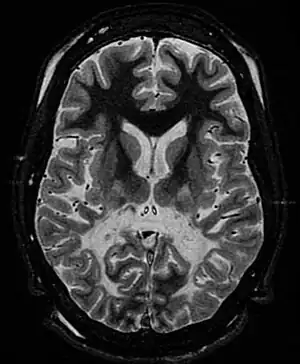

| White matter, with reduced volume and increased signal intensity. The anterior white matter is spared. Features are consistent with X-linked adrenoleukodystrophy. | |

The Loes score is a rating of the severity of abnormalities in the brain found on MRI. It ranges from 0 to 34, based on a point system derived from the location and extent of disease and the presence of atrophy in the brain, either localized to specific points or generally throughout the brain. A Loes score of 0.5 or less is classified as normal, while a Loes score of 14 or greater is considered severe. It was developed by neuroradiologist Daniel J. Loes MD and is an important tool in assessing disease progression and the effectiveness of therapy.[12]